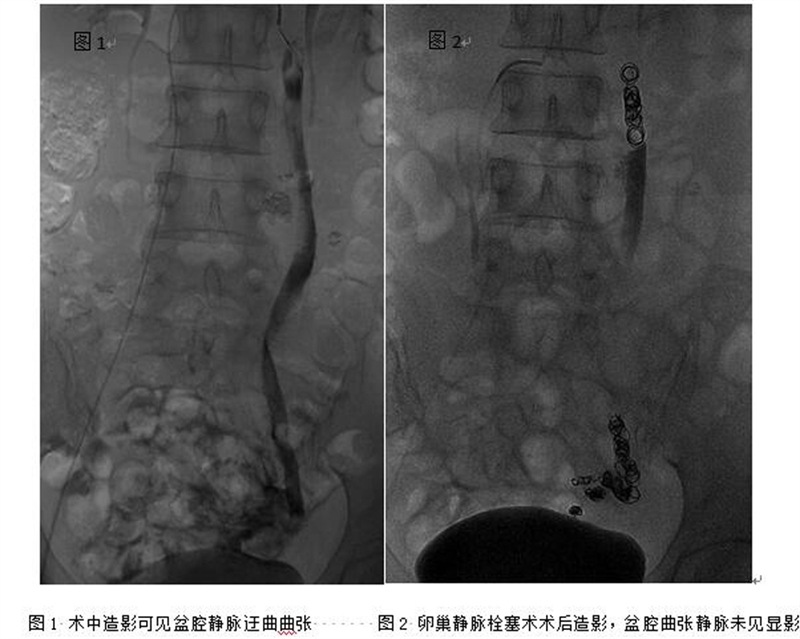

??? 在與徐女士充分溝通后,陸煒決定用導(dǎo)管靜脈栓塞術(shù)來(lái)幫助徐女士解除病痛。手術(shù)進(jìn)展很順利,術(shù)后,徐女士下腹部疼痛癥狀明顯好轉(zhuǎn),目前已康復(fù)出院。據(jù)悉,這是全市首例完成的導(dǎo)管靜脈栓塞術(shù)治療盆腔淤血綜合征。

??? 目前,國(guó)內(nèi)外推薦盆腔淤血綜合征首選經(jīng)導(dǎo)管栓塞療法,該法屬于微創(chuàng)療法,無(wú)需開(kāi)刀,只需要在患者的大腿上打一個(gè)針眼大的小孔,經(jīng)血管使用栓塞材料堵塞病變血管,就能從根本上解除病因。導(dǎo)管栓塞療法治療PCS具有療效好、復(fù)發(fā)率低的優(yōu)點(diǎn),目前已得到國(guó)內(nèi)外的廣泛認(rèn)可和推崇,術(shù)后可明顯改善患者盆腔疼痛、下肢腫脹、性交疼痛、抑郁等癥狀。